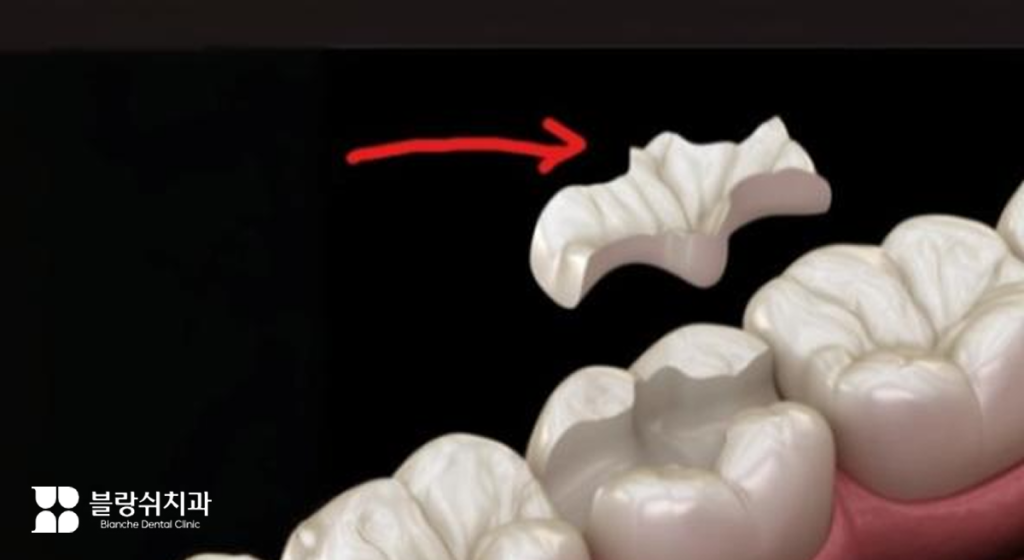

반면 온레이는 치아 씹는 면 일부까지 덮는 방식으로, 전체 크라운 씌우기 전 단계의 부분 보강 치료라고 이해하시면 돼요. 인레이보다 덮는 범위가 넓지만, 최대한 치아 보존 범위를 넓게 유지할 수 있다는 점이 있죠.